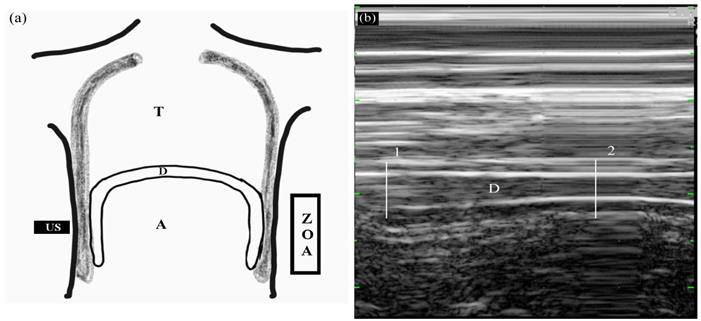

Diaphragmatic thickening was measured using M-mode in the zone of apposition (ZOA) to the rib cage from 8th to 9th intercostal space (Figure 2). The US transducer was placed at the anterior axillary line between the 8th and 9th ribs. At that time, real-time diaphragmatic movement could be recorded in M-mode. The diaphragmatic muscle was observed as an-echogenic central layers between two echogenic layers consisting of the diaphragmatic pleura and peritoneum using linear 10 MHz probe. Diaphragmatic thickening was measured by placing electronic calipers inside the two hyper-echoic lines. Two different phases of diaphragmatic thickening were measured at end-inspiration (TEI), and end-expiration (TEE). Diaphragmatic thickening faction (DTF) representing diaphragmatic efficiency was calculated as follows:

Figure 2

Measuring diaphragmatic thickening using M-mode in the zone of apposition (ZOA) to the rib cage from 8th to 9th intercostal space. (a) Frontal section of the chest wall illustrating the functional anatomy of the diaphragm. A, abdomen; D, diaphragm; T, thoracic cage; US, ultrasound probe; ZOA, zone of apposition. (b) Recording of changes in diaphragm thickening during spontaneous breathing using M-mode tracing. 1, end-inspiration; 2, end-expiration; D, diaphragm.